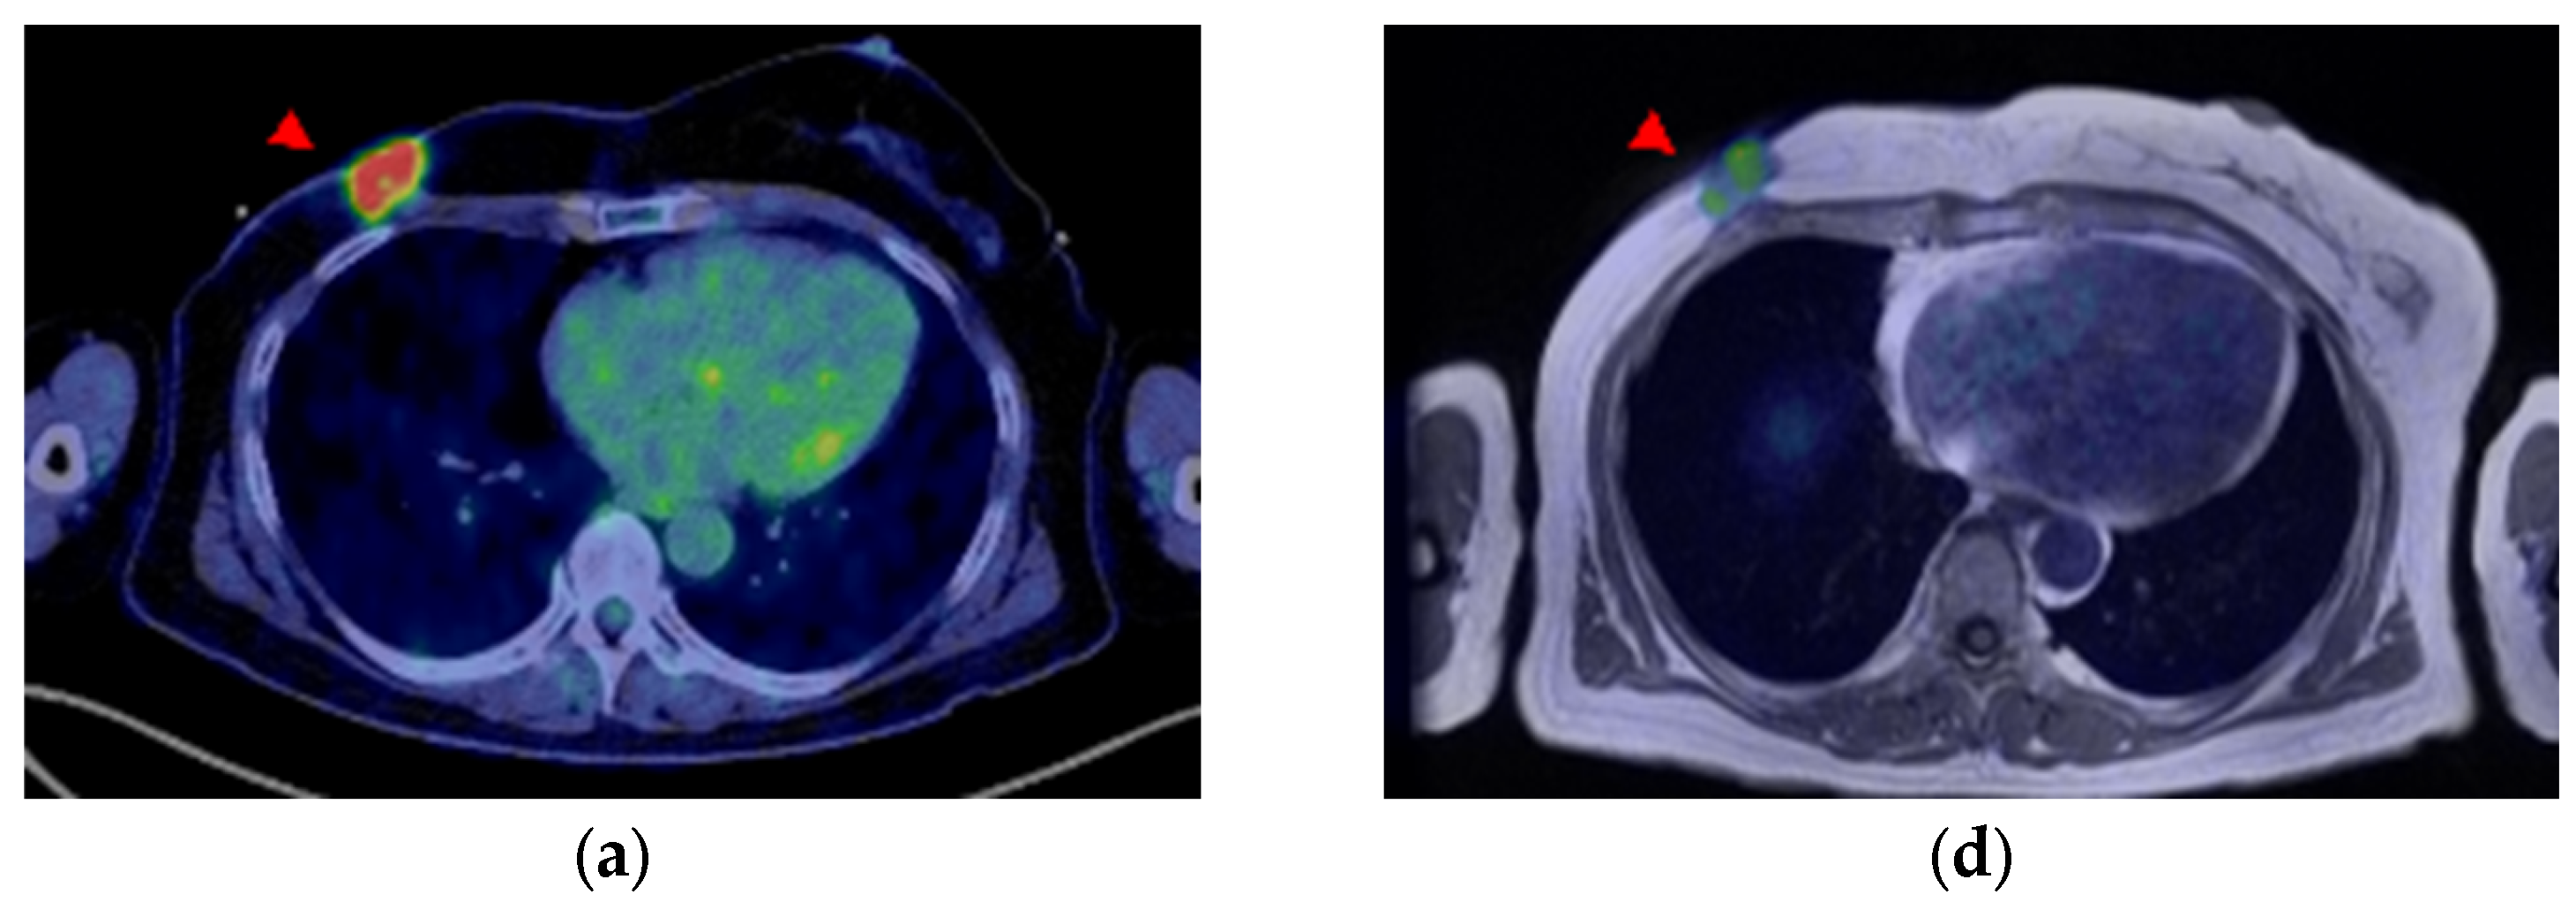

A 58-year-old woman was diagnosed with ER-positive right breast cancer on histopathological examination using H&E staining and IHC (ER 80%, PgR 80%, HER2 score1, MIB-1 index 10%). She underwent pretreatment [18F]FDG PET/CT for staging. In addition to intense [18F]FDG uptake in the primary breast tumor (Figure 4a and Figure 5a, red arrowhead), increased [18F]FDG uptake was observed in level I (Figure 4a and Figure 5b, red arrow) and level II contralateral axillary lymph nodes (Figure 4a and Figure 5c, white arrow). Since she was vaccinated against COVID-19 (the Moderna COVID-19 vaccine) in her left deltoid muscle 12 days before the [18F]FDG PET/CT scan, the [18F]FDG-avid contralateral axillary lymph nodes were considered as vaccine-associated hypermetabolic lymphadenopathy. She had undergone surgery for the right axillary ganglion, and we suspected possible altered lymphatic drainage. Four weeks after [18F]FDG PET/CT, she underwent [18F]FES PET/MRI to evaluate the ER expression of the lesions. [18F]FES PET/MRI showed moderate [18F]FES uptake in the ER-positive right breast cancer (Figure 4b and Figure 5d, red arrowhead) and high [18F]FES uptake in the level I contralateral axillary lymph node (Figure 4b and Figure 5e, red arrow), and her condition was finally diagnosed as synchronous contralateral axillary lymph node metastasis (CAM). In contrast, the level II lymph nodes did not show significant [18F]FES uptake (Figure 4b and Figure 5f, white arrow). Although histopathological evidence was not available, the lymph node with FES accumulation diminished after treatment with an aromatase inhibitor (Letrozole) and a molecularly targeted agent (Abemaciclib), indicating lymph node metastasis. Uterine leiomyoma with [18F]FES uptake was also observed in this patient (Figure 4b, yellow arrowhead).

Figure 5.

(a–c) [18F]FDG axial PET/computed-tomography (CT)-fused images and (d–f) [18F]FES PET/MR-fused images of right breast cancer and multiple contralateral axillary lymph nodes. ((a,d), arrowhead) The right breast cancer shows uptake on both [18F]FDG and [18F]FES PET. ((a–c), arrows) The multiple contralateral axillary lymph nodes show intense [18F]FDG uptake. ((e), red arrow) The level I contralateral axillary lymph node shows intense [18F]FES uptake, whereas ((f), white arrow) the other node does not show significant uptake.